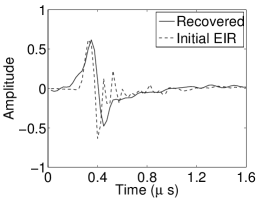

The reconstruction region ( mm2) was represented by pixels with pixel size mm in each dimension. The initial guess of the EIR employed in the VP algorithm was different than the EIR that was assumed when generating the simulated data. This served to simulate a situation in which an experimentally measured EIR contained errors.

Each element in a real-world transducer array possesses its own EIR. In practice, the differences between the EIRs are sometimes neglected and an EIR corresponding to a single element may be used to represent all elements in the array. In some of the studies below, the EIR employed to initialize the VP algorithm (EIR-2 in Figure 1(b)) and the EIR employed to produce the simulated measurements (EIR-1 in Figure 1(b)) were experimentally measured from two different transducer elements in a circular transducer array (see Sec. VI-B). EIR-1 was measured by temporally integrating the PA signal produced by a point source positioned at the focus of the transducer. EIR-2 was measured by use of the method reported in [RNR2011]. In order to investigate the sensitivity of the VP algorithm to the initialization of the EIR, we employed different EIRs obtained by degrading EIR-1 as described later. When solving the sub-problem in Line-2 of Algorithm 1, was initialized as the zero vector. Algorithm 1 was terminated after 500 iterations, since it was observed that the changes in the reconstructed images with more iterations were negligible. When implemented by use of a single core of an Intel Xeon E5-2640 CPU, each iteration required approximately 7s to complete.

Figure 2(a) shows the image reconstructed by use of the conventional iterative method that utilized a system matrix based on EIR-2. Different values of the regularization parameter from the interval were considered. The reconstructed image with the value of that minimized the RMSE was chosen to represent the best performance of the conventional iterative method. Figure 2(a) and the profile in Figure 2(c) demonstrate that the use of an inaccurate EIR can result in strong artifacts and distortions in images reconstructed by use of the conventional methods.

When the VP algorithm was applied, different values of the regularization parameter from the interval and from the interval were considered. The image that minimized the RMSE was chosen and displayed in Figure 2(b). As revealed by this image and the profiles in 2(c), the VP algorithm yielded an image with fewer artifacts and distortions, and image fidelity was improved as reflected by the reduced RMSE.

Figure 7(a) reveals that use of the inaccurate EIR in the conventional iterative method created strong artifacts and distortions. Figures 7(b) confirms that the artifacts and distortions were significantly mitigated when the VP method was employed. Image profiles for both cases are shown in Figures 7(c). The overall accuracy of the recovered EIR, shown in Figure 7(d) and 7(e), was improved, but it contained spurious oscillations.